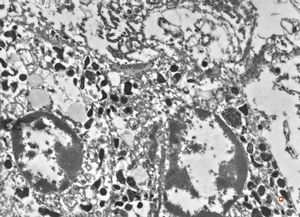

F,68y. | spleen - undefined myelinoid inclusions - clin. susp. leukemia

F,68y. | spleen - myelinoid inclusions - clin. susp. leukemia